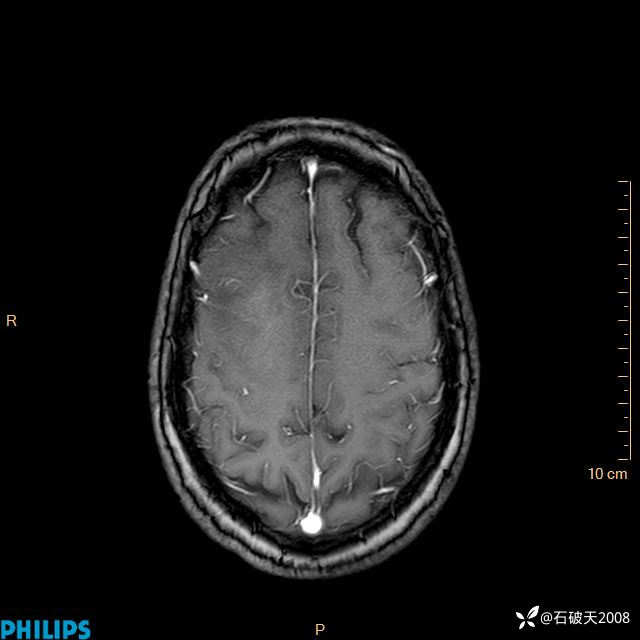

2024.2.21MR

增强轴位